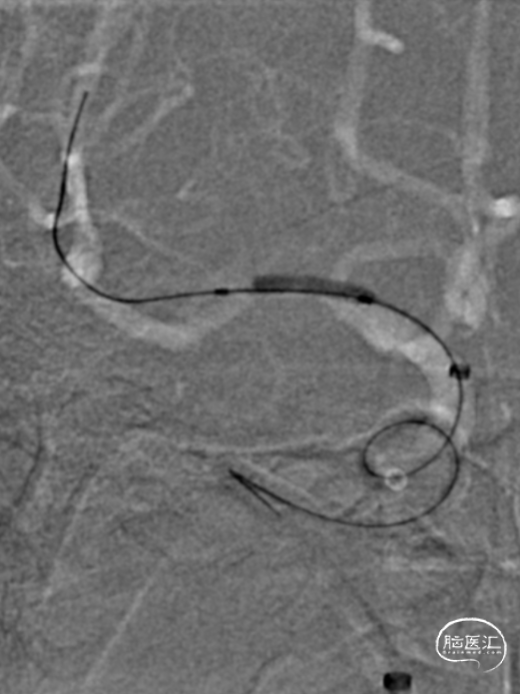

手推冒烟见RICA C1-C5段显影,C5段以远闭塞。将Pro-18微导管在Synchro(0.014×200mm)微导丝引导下送至RMCA M2段,微导管冒烟示远端血流通畅。将Trevo XP(4×20mm)取栓支架于M1段远端向RICA末端释放,采用SWIM技术取栓1次,并同时将中间导管送至颈内动脉末端抽吸。抽出数枚暗红色血栓。

造影见RICA再通,RMCA M1段近端重度狭窄,约90%。

观察10分钟后,狭窄较前加重,局部不规则充盈缺损。术中即刻DynaCT未见造影剂染色。